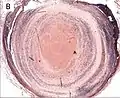

Thrombus showing circumferential lines of Zahn.

Recent pulmonary thromboembolus exhibiting prominent lines of Zahn. The pale areas consist of fibrin and platelets; the red areas consist of erythrocytes.